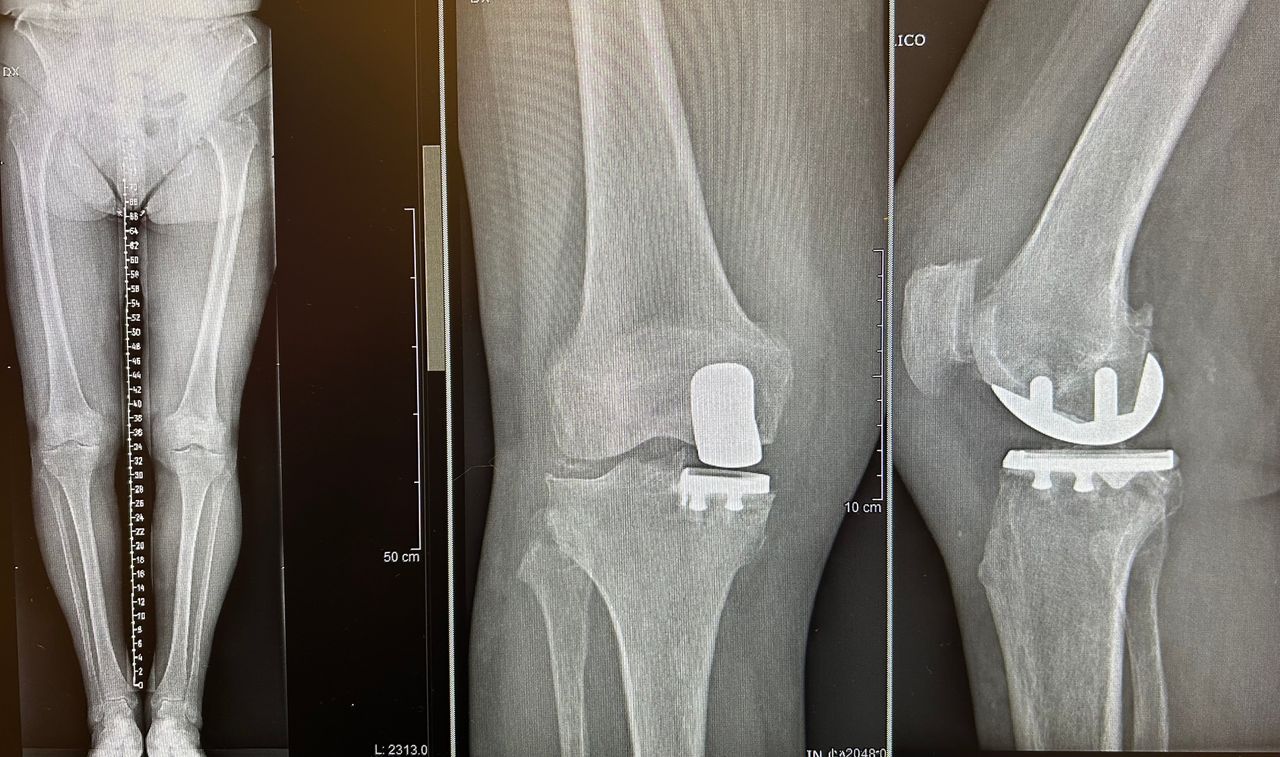

• Chirurgia del ginocchio

Per una maggiore completezza della visita è utile avere a dispozione almeno una Radiografia standard o Risonanza Magnetica recenti.

Il dottore Luciano è un ortopedico in cui si coniugano perfettamente professionalità, umanità e grande attenzione, merce rara! Ho effettuato protesi completa di anca e femore in chirurgia miniinvasiva.

Intervento riuscitissimo(e il mio era un caso piuttosto complesso!), ho camminato bene dai primi giorni, il dottore, con eccesso di scrupolo, ha seguito il decorso e le medicazione fino alla completa guarigione, sempre reperibile per qualsiasi imprevisto. Immensamente grata.